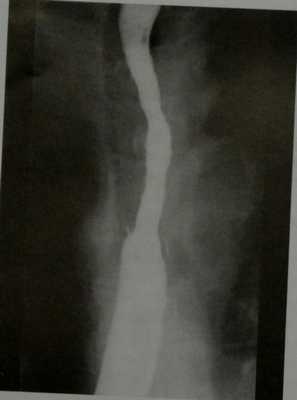

Рентгеноскопия с контрастированием бариевой взвесью: дивертикул Ценкера, сдавливающий пищевод. В левой передней прямой проекции визуализируется дивертикул слева от средней линии. В правой боковой проекции дивертикул выглядит как заполненный барием мешок позади пищевода.

(Справа) На рентгенограмме в боковой проекции, полученной во время проглатывания бариевой взвеси, визуализируется мешковидное выпячивание со стороны задней стенки в области глоточно-пищеводного перехода. (Слева) На рентгенограмме, выполненной во время рентгеноскопии глотки и пищевода с бариевой взвесью, визуализируется большой дивертикул в области глоточно-пищеводного перехода, распространяющийся в средостение. Пищевод смещен в сторону, его просвет сужен за счет объемного воздействия дивертикула. Обратите внимание, что контрастное вещество определяется также и в трахее, попав туда в результате аспирации.

а, b Дивертикул Ценкера большого размера. Рентгенография в прямой (а) и боковой (b) проекциях с контрастированием бариевой взвесью. На боковой проекции визуализируется сужение на уровне перстневидно-глоточной мышцы.